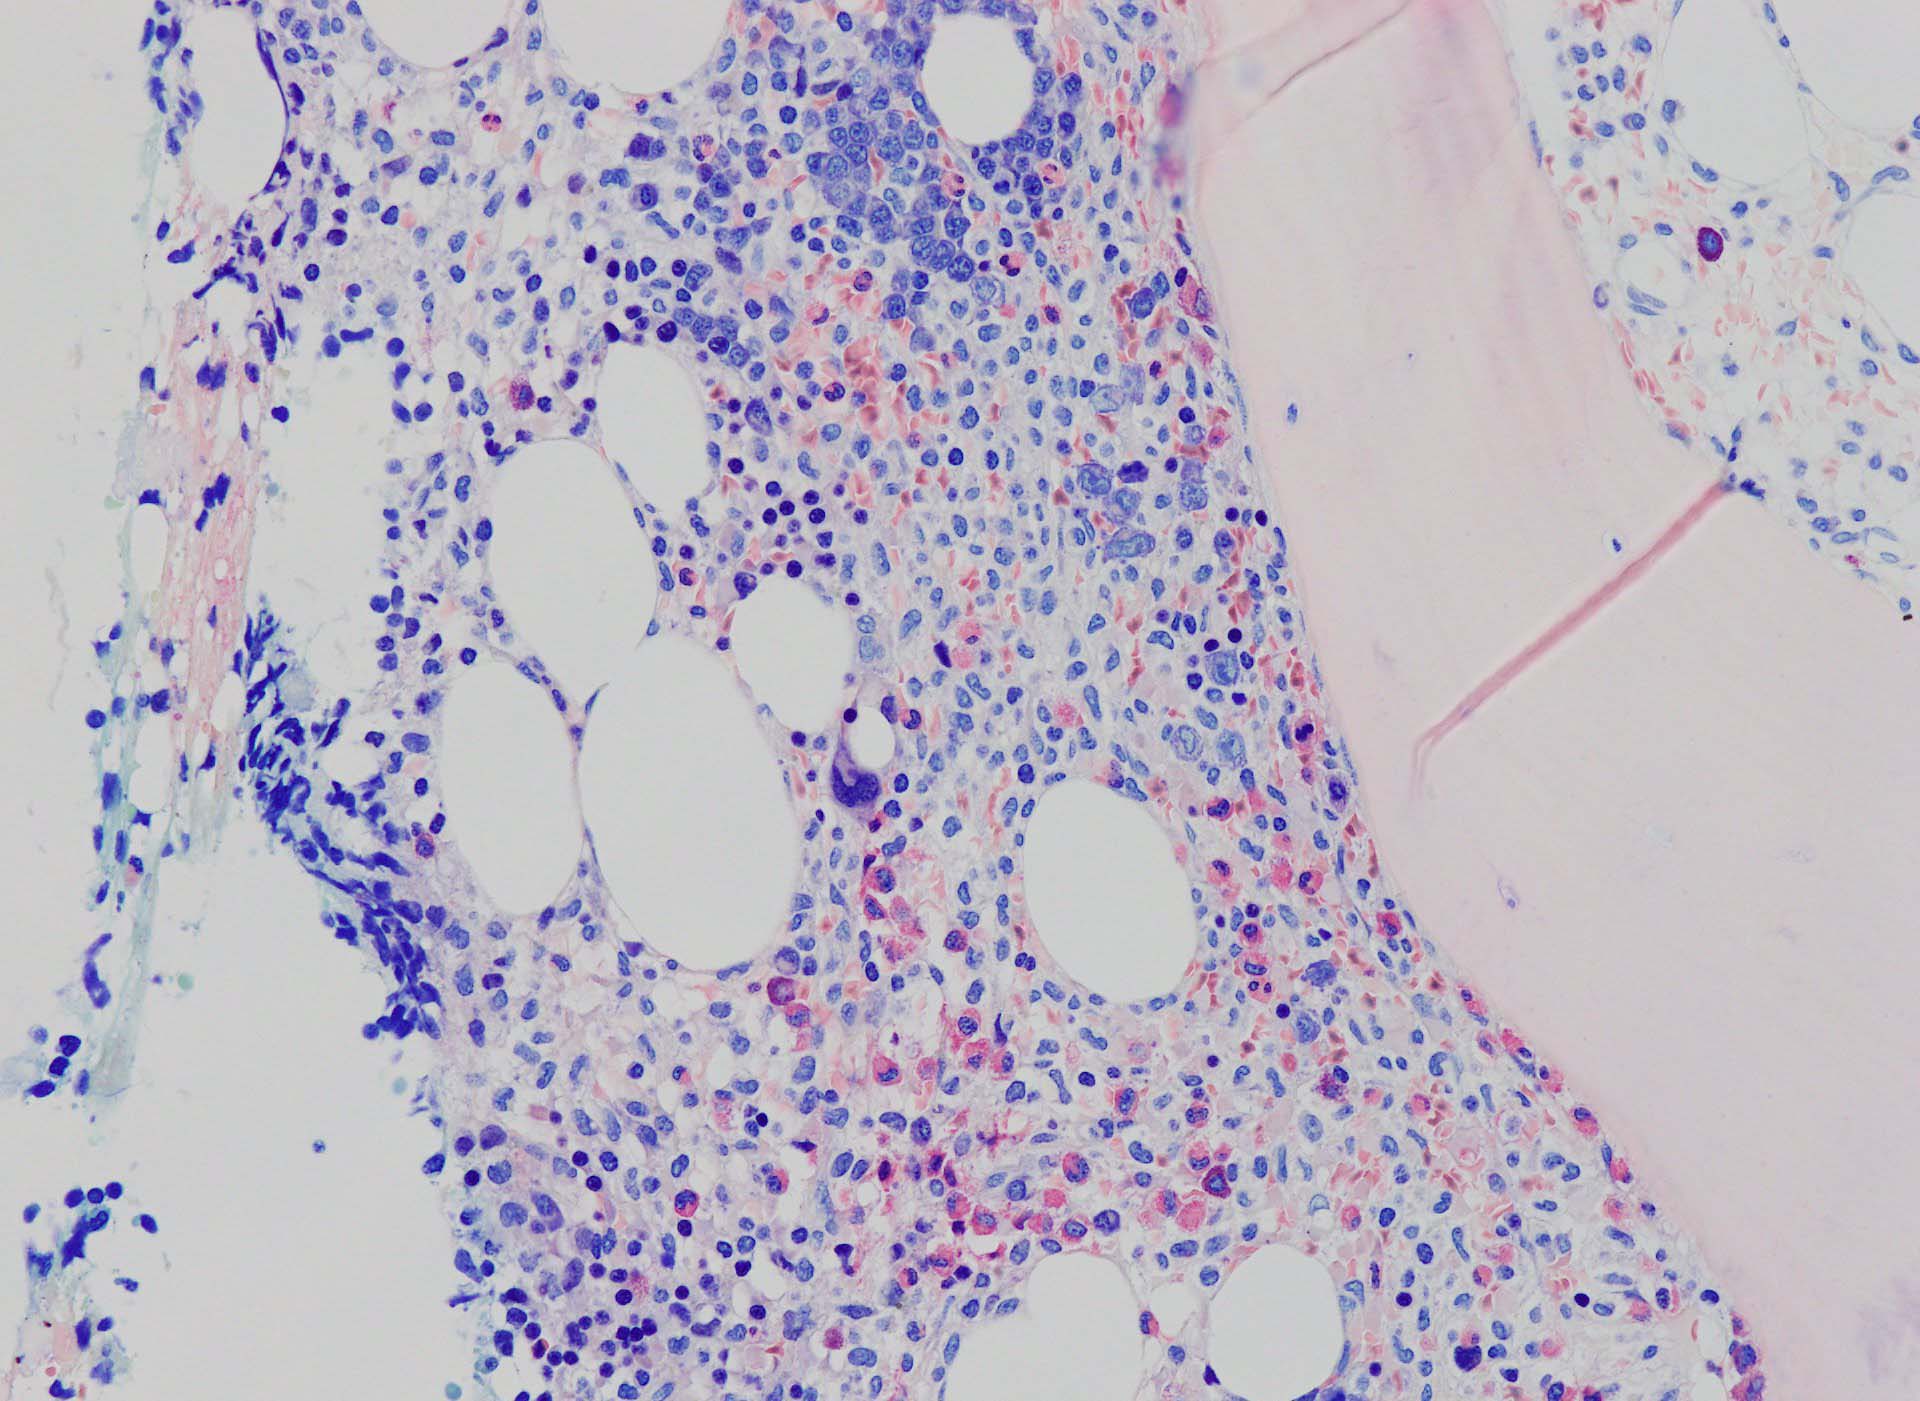

ASD-Giemsa陰性の細胞がシート状に増殖する. 核はクロマチン濃染, 核小体は不明瞭.類円形, 卵円形, くびれを持つ多稜形核, 長円形いびつで屈曲した核, など多彩. 細胞質は淡清色調, 広く淡明. 赤芽球血島は幼若赤芽球のみで形成される異形成像を示す. やや離れて成熟赤芽球が疎な集簇を示す.

Ag染色では, 疎な弾性線維が増生し,増殖細胞を小胞巣状に分画するいわゆる「lymphomatoid pattern」を呈する. 本例では, Mgkに異形成所見がある.

Immunophenotype

骨髄生検組織を使ったFCMのため, 細胞数が少数であるがCD19, CD20陽性のB-cellが優位で, lambda LC > kappa LCの偏倚がみられclonalな増殖が考えられる. B-cellはCD11c, CD25も発現している. Hairy cell leukaemiaが疑われる. CD103はこのFCMセットには組み込みがなかった.

Hairy-FCM のコピー.jpg ASD-up-PAX5ok.jpg びまん性にPAX5陽性の小型B-cellsが増殖している.

増殖細胞はCD20(相変わらずべったり染まる), CD19, PAX5陽性 CD25陽性.